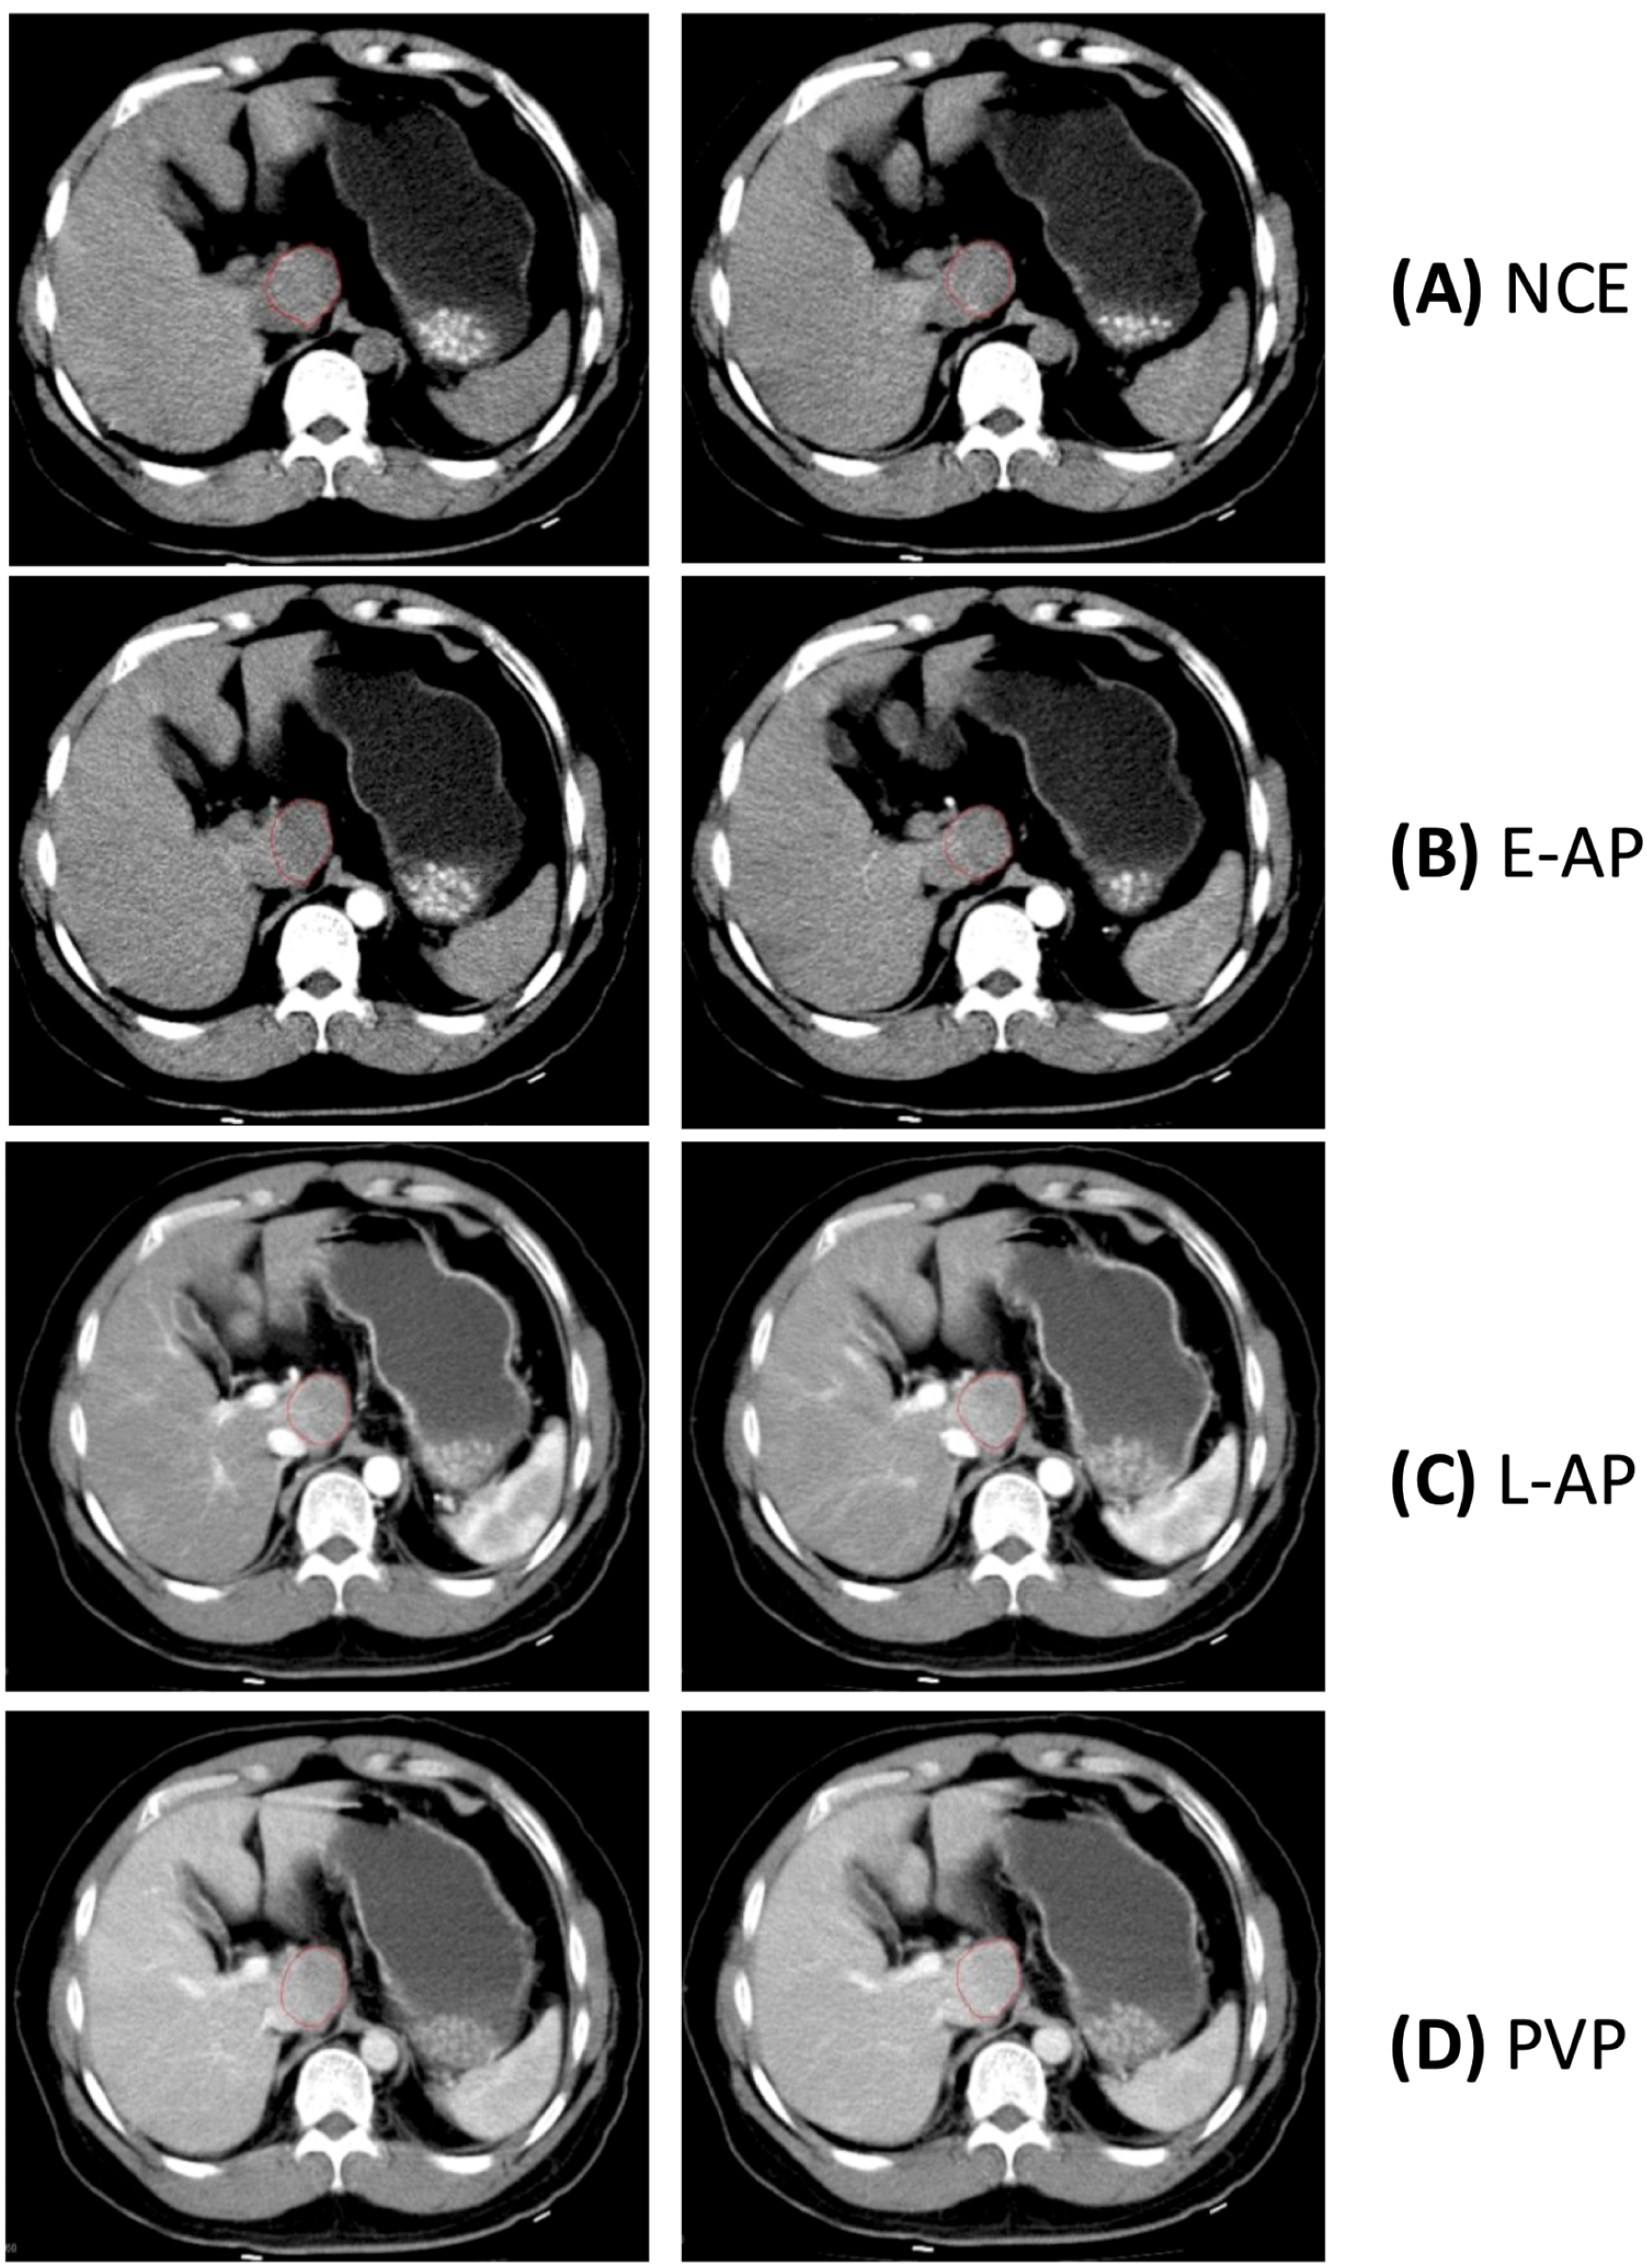

2.2. Reference Standard for Contrast Enhancement Phases

2.3. Lesion Segmentation and Measurements